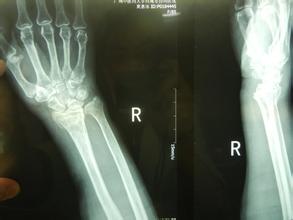

桡骨远端骨折非常常见,都有哪些原因引起的呢?

1、跌倒后腕关节处于背伸,手掌着地,重力集中于桡骨远端松质骨处而引起骨折。老年人由于骨质疏松,轻微外力即可造成骨折,大多数是粉碎骨折。这是最常见的一种桡骨远端骨折的原因。

2、跌倒后手背着地,骨折远端向掌侧及尺侧移位。这种情况比较少见。

3、跌倒后手掌或手背着地,重力向上传递后近排腕骨撞击引起桡骨关节面骨折,桡骨下端掌侧或背侧形成关节面软骨的骨折块,骨块常向近侧移位,引起腕关节脱位。青壮年发生几率高。

桡骨远端骨折应及时去正规医院就医,根据骨折的严重性合理的治疗。骨折治疗期间患者要注意肩、肘及手指的活动锻炼,锻炼要适量。尤其老年人通过锻炼预防肩关节僵硬。同时还要注意桡骨远端骨折的并发症。部分患者愈合较好,而损伤较重患者或者治疗不当容易引起骨骺早期闭合者,长期不矫正就可出现尺骨长、桡骨短,手腕桡偏的曼德隆样畸形。此并发症给患者身心带来痛苦,因此应及时矫正和处理。